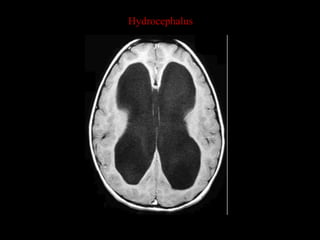

Hydrocephalus